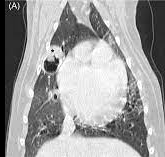

보통 이런식으로 폐야에 bullar 같은 공기주머니가 형성되어 있으면 만성 기관지염이나 장기간에 걸친 기침등으로 인해 발생한 양성 병변인 bullar를 의심한다.

하지만 이런 bullar의 일부는 폐의 암종에 의해서 발생할 수 있으며 그에 대한 논문이 다음과 같다.

즉, bullar로 치부하지 말고 CT 촬영을 통해 종괴 가능성 평가를 할 필요가 있다는 것을 실증한 논문임과 동시에

어차피 bullar가 발생하더라도 시간이 흐를 수록 폐야를 모두 먹어 파열로 인한 기흉으로 급사 가능성이 있는 bullar 또한 종양의 가능성이 있으니 bullar가 발생하는 경우 조기에 폐엽 절제술을 통해 치료할 필요가 있다는 근거를 하나 추가한 샘이다.